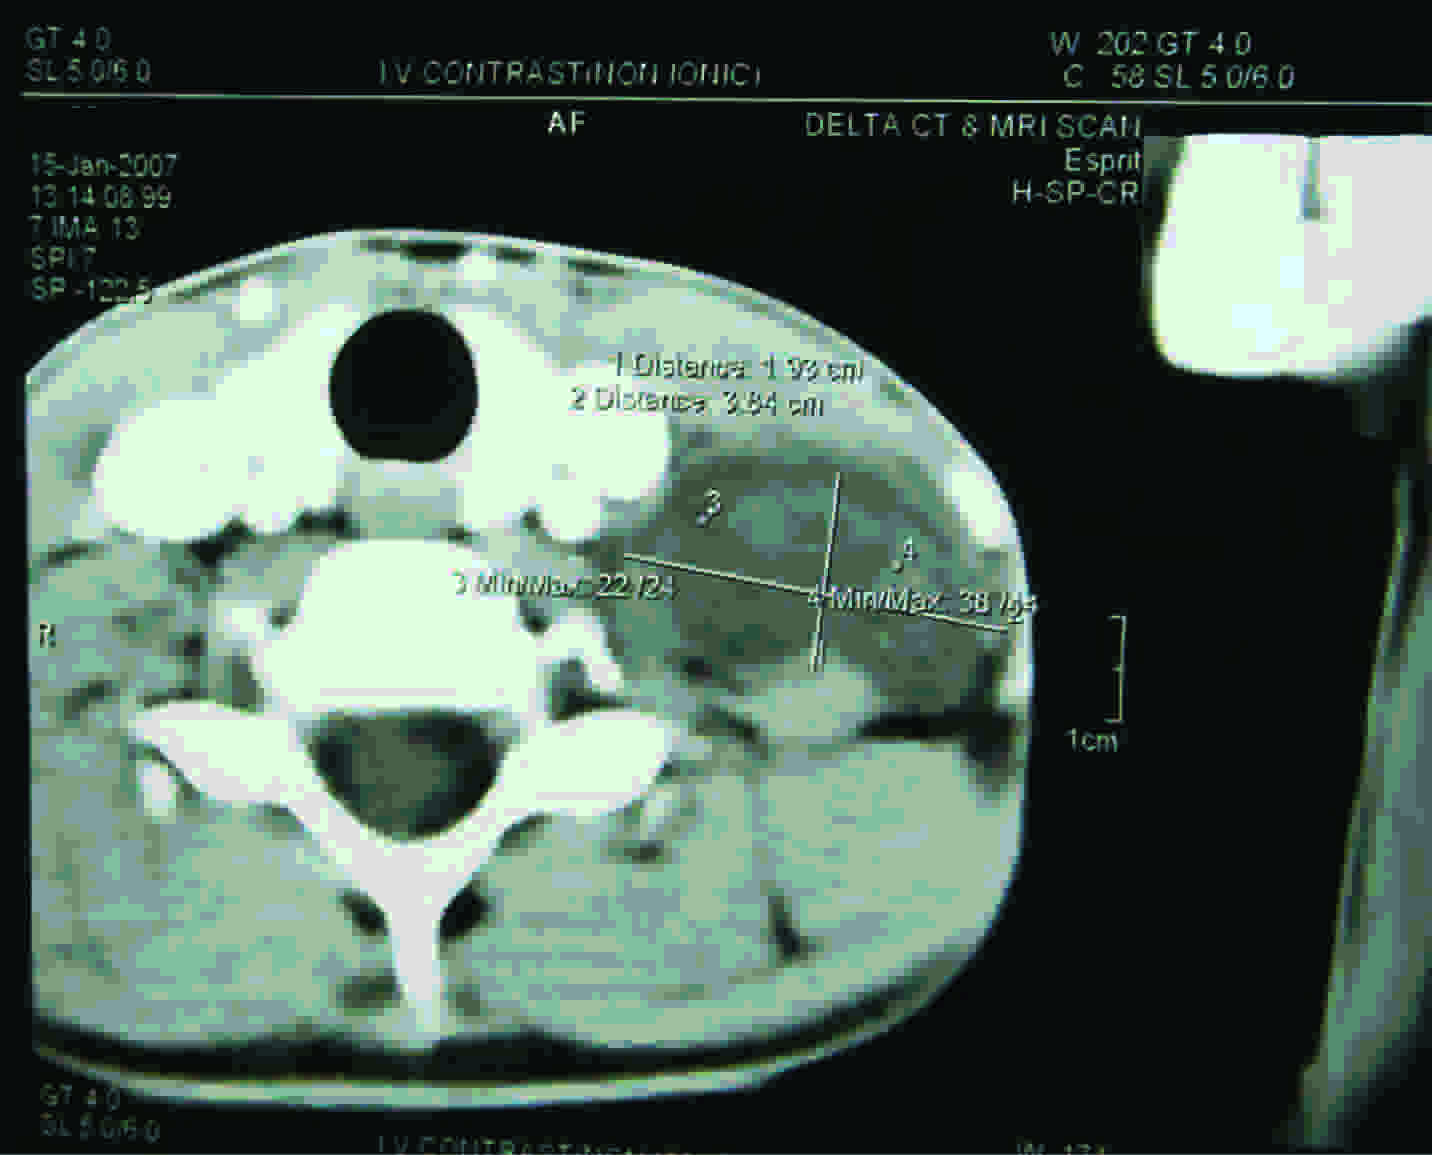

The patient underwent complete blood count and urine culture examinations, which were found to be within normal limits. Ultrasonography was advised to know whether the tumour was located between the jugular vein and the carotid artery. Magnetic Resonance Imaging (MRI) was done with the use of Gadolium based contrast media, for determining the exact nerve of origin [Table/Fig-2].

MRI scan showing the location and dimension of Schwannoma

Imaging studies help in the accurate diagnosis of schwannomas, with a reasonably good accuracy. The modalities like MRI scans are very helpful in identifying the tumours and their correlations with the surrounding vascular structures, muscles, and nerves [4]. In addition, preoperative imaging provides information on the tumour size, location, extent and the surrounding anatomy, and it enables the surgical planning [2].